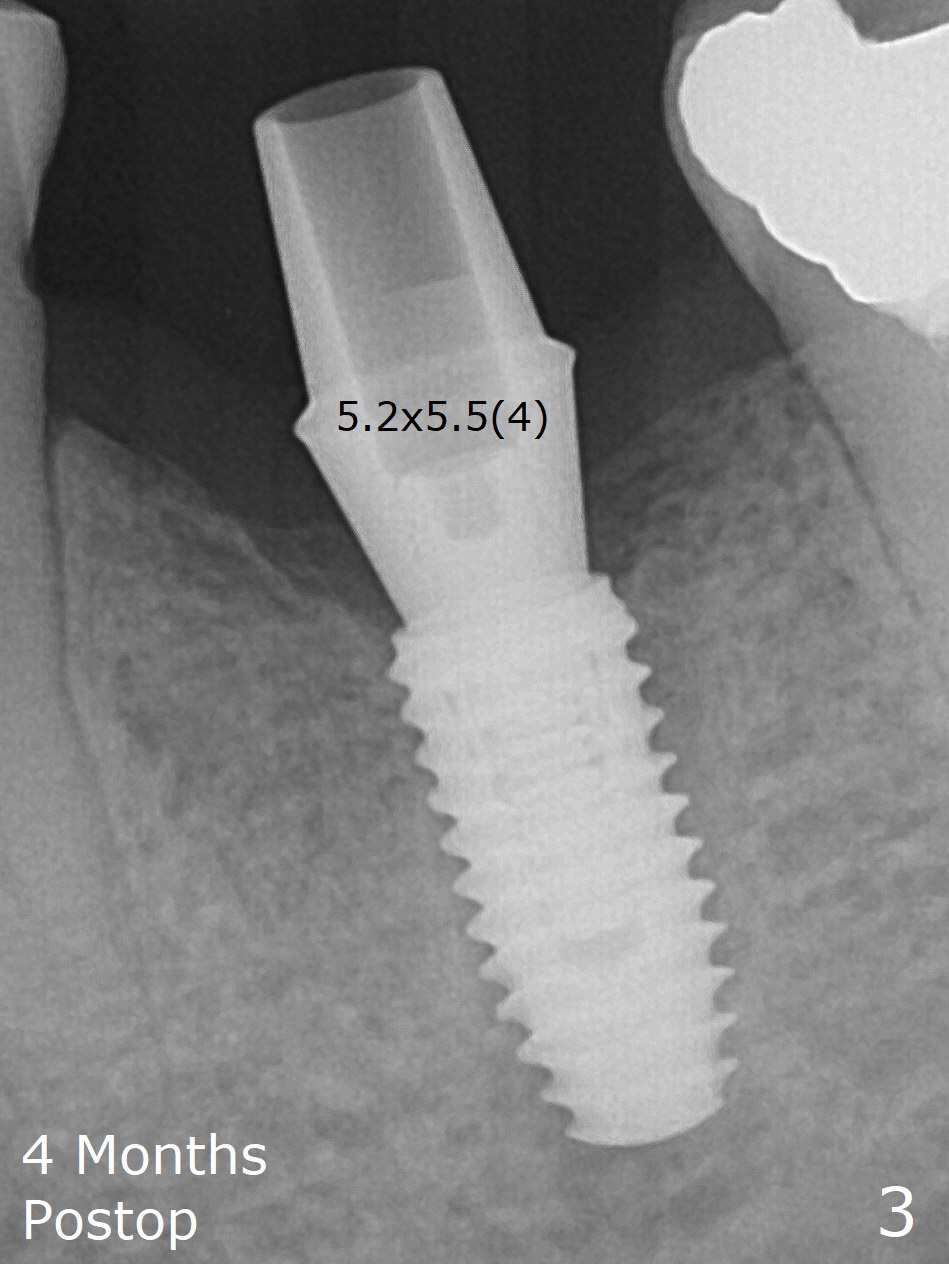

Due to low bone density associated with no bone graft after extraction and possible accessory nerve, osteotomy at #19 is underprep in diameter (3.5 vs. 4.0x8.5 mm), but overprep finally in length (3.5x10 mm) with 1 ampule of Lidocaine. Insertion torque associated with 4.0 and 4.5 mm cortical taps and 4.5x10 mm implant (Fig.1) is between 30-55 Ncm. Since the implant is covered by buccal and lingual bone associated with deep placement, no bone graft is conducted. The lingual gingiva has minor laceration near the access. Periodontal dressing is applied. It remains in place a week postop due to retention associated with the healing abutment (Fig.2 *). A long abutment is placed for restoration 4 months postop (Fig.3), increasing the chance of abutment screw loosening (as compared to immediate implant) if the abutment is incompletely seated.